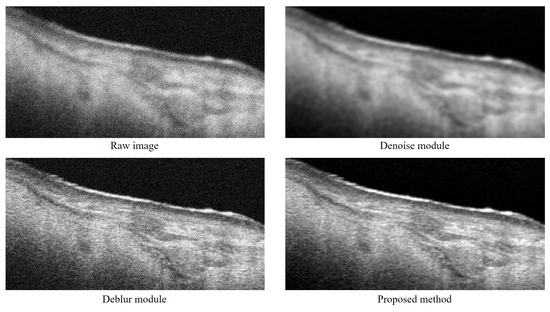

4.2. Performance Comparison Results

| Metrics (Mean ± std) | ||

|---|---|---|

| Method | PSNR | SSIM |

| Original images | 8.94 ± 2.01 | 0.34 ± 0.14 |

| BM3D | 24.11 ± 1.04 | 0.71 ± 0.08 |

| DnCNN | 23.99 ± 2.70 | 0.78 ± 0.24 |

| DRGAN | 16.77 ± 1.04 | 0.61 ± 0.10 |

| OSE | 26.71 ± 2.21 | 0.81 ± 0.16 |

| Mean Processing Time (s) | ||

| Method | CPU | GPU |

| BM3D | 45.69 | - |

| DnCNN | 11.14 | 0.17 |

| DRGAN | 3.77 | 0.14 |

| OSE | 3.86 | 0.12 |